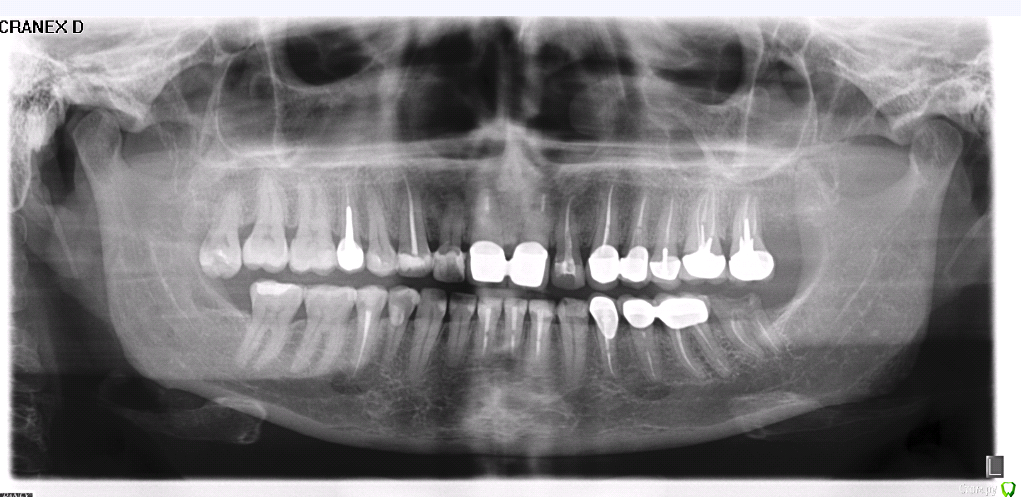

светлана1706 Опубликовано 25 июня, 2020 Поделиться Опубликовано 25 июня, 2020 Здравствуйте.помогите,пожалуйста!!! Снизу слева сломалась коронка, остался корень,зуб под имплант.одновременно внизу на передних зубах огромные пломбы уже под кариесом.один врач говорит надо вначале коронки на 6 передних зубов,другой-ставьте имплант! как лучше? посоветуйте! Ссылка на комментарий

колесников Опубликовано 26 июня, 2020 Поделиться Опубликовано 26 июня, 2020 Здравствуйте! Вначале восстанавливаются жевательные зубы,прикус,после эстетика Ссылка на комментарий